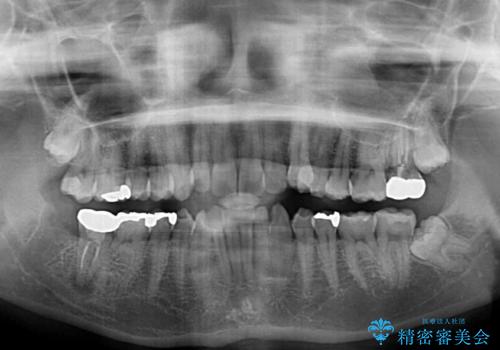

- 上下の前歯のデコボコを治したいとのことで来院された患者様です。

上下顎ともにIPR(歯と歯の間を削る)と歯列全体の拡大によって叢生が解消するように設計し、インビザラインにより治療を行うこととしました。